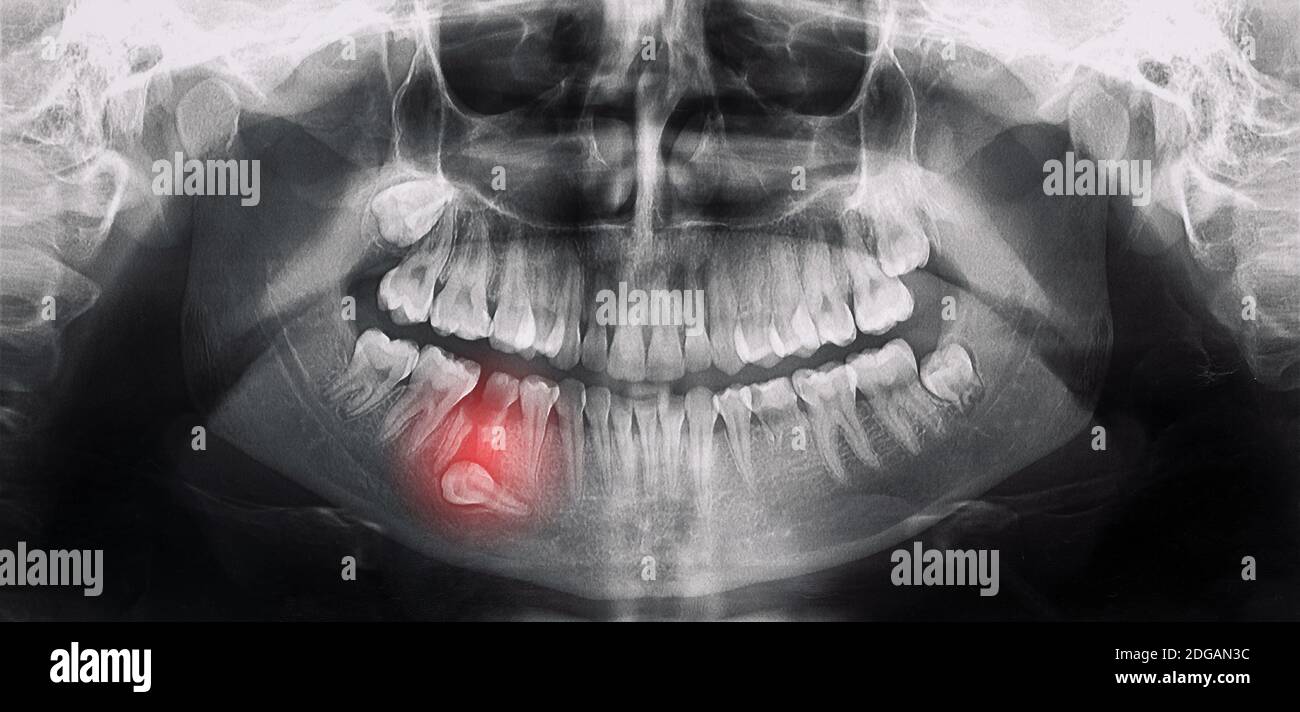

Horizontal Inflamed Wisdom Tooth On Panoramic Dental Tooth X-ray

www.dreamstime.comWISDOM TOOTH, X RAY Stock Photo - Alamy

www.dreamstime.comWISDOM TOOTH, X RAY Stock Photo - Alamy

www.shutterstock.comWisdom Teeth Dental X Ray Image. Tooth Pain Stock Photo - Alamy

www.shutterstock.comWisdom Teeth Dental X Ray Image. Tooth Pain Stock Photo - Alamy

www.cigna.comX-ray Oral Image With An Inflamed Wisdom Tooth Close-up Stock Photo

www.cigna.comX-ray Oral Image With An Inflamed Wisdom Tooth Close-up Stock Photo

Fillings teeth problematic extraction wisdom ray alamy. Wisdom teeth dental x ray image. tooth pain stock photo. X-ray oral image with an inflamed wisdom tooth close-up stock photo